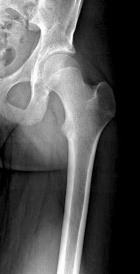

J.G. - 14 year old male c/o left posterior thigh mass for eight months. His mother noticed the mass, but no ecchymosis, after he fell while running hurdles. He complains of pain only when running long distances, and with prolonged pressure. It has decreased in size only minimally. No F/C.